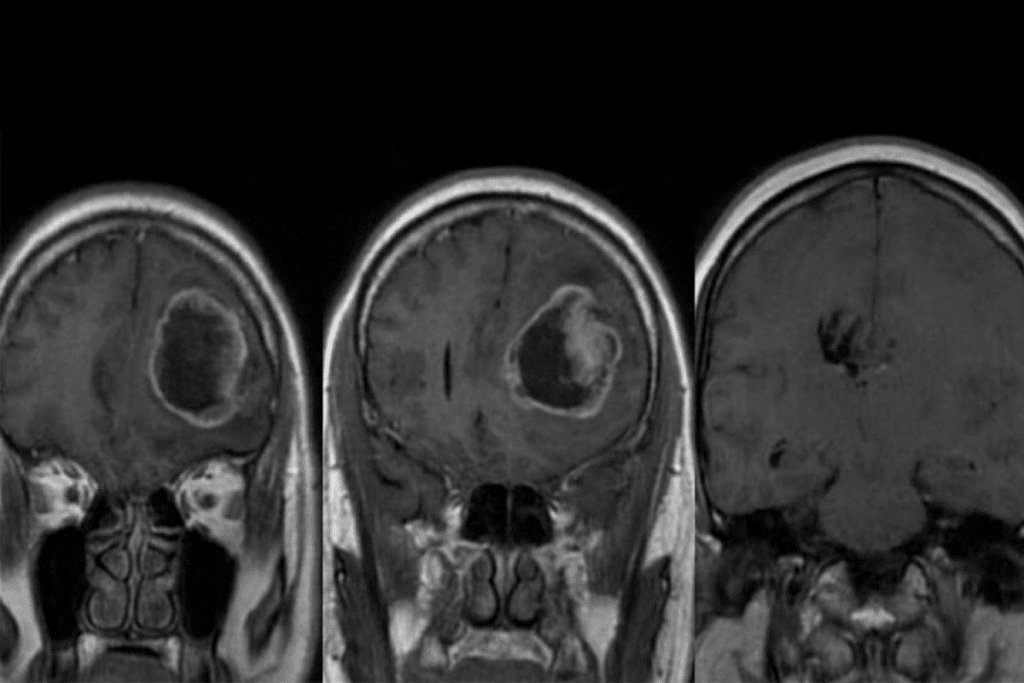

Brain MRI Results: What They Mean

Brain MRI scans can show many things, from nothing to serious problems. It’s important to understand what they mean for your health.

Common Brain MRI Findings and Their Significance

Scans can find issues like white matter changes and cerebral atrophy. They might also spot cysts or aneurysms. Some findings are okay, but others need more attention.

White matter changes are common in older people. They might be due to aging or health issues. Cerebral atrophy, or brain shrinkage, is also normal but can sometimes mean a health problem.

Potentially Serious Brain Abnormalities

Some MRI results show serious issues that need quick action. These include signs of stroke, tumors, or multiple sclerosis. Doctors and radiologists must carefully look at these to decide what to do next.

For example, if an MRI shows a stroke, acting fast can help a lot. Finding a tumor might mean talking about treatments like surgery or chemotherapy.

Follow-up Recommendations for Brain MRI Findings

What happens next after a brain MRI depends on the results. For minor findings, doctors might suggest waiting and watching with more scans. If a serious condition is found, a treatment plan will be made with specialists.

It’s key for patients to talk to their doctors about MRI results. This way, they can understand what the findings mean and what to do next. This teamwork helps ensure patients get the best care for their situation.